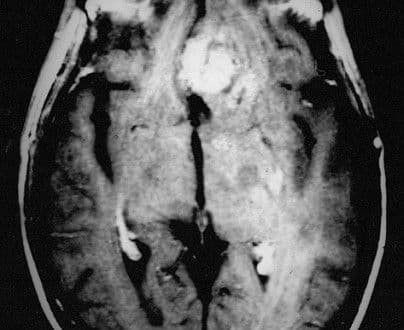

Przyczyny rozwoju stwardnienia rozsianego są nadal nie do końca poznane. Wiadomo, że istotą choroby jest powstawanie rozsianych ognisk demielinizacji w obrębie mózgu oraz rdzenia kręgowego.

Zapalenie mózgu (ang. encephalitis) jest rzadką, ale bardzo poważną chorobą zapalną, która stanowi zagrożenie życia pacjenta.